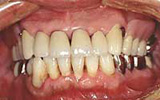

| 主訴 | 左右奥歯がぐらぐらで物が噛めない |

| 年齢・性別 | 60代 男性 |

| 治療説明 | ぐらぐらの奥歯は抜歯し、すぐに仮の入れ歯をお作りします。 最終的に義歯のフレームを金属で作ることで、薄く丈夫にできます。 義歯であっても異物感が少ない方法を選択しました。 |

| 治療費 | 合計額:422,000円+税 金属床(7歯) 110,000+17,000×6=212,000円 クラスプ(3ヶ所) 50,000×3=150,000円 人工歯(7歯) 30,000=5,000×6=60,000円 |

| 治療期間 | 治療期間:3ヶ月 抜歯後すぐに仮義歯を入れ、抜いた傷がきれいに治るまでクッション材を使いました。 2か月後精密な型どりをして薄く丈夫な金属を使った義歯を作りました。 異物感も少なく、熱を伝導するので食事をおいしく食べることができると喜んでいただけました。 |